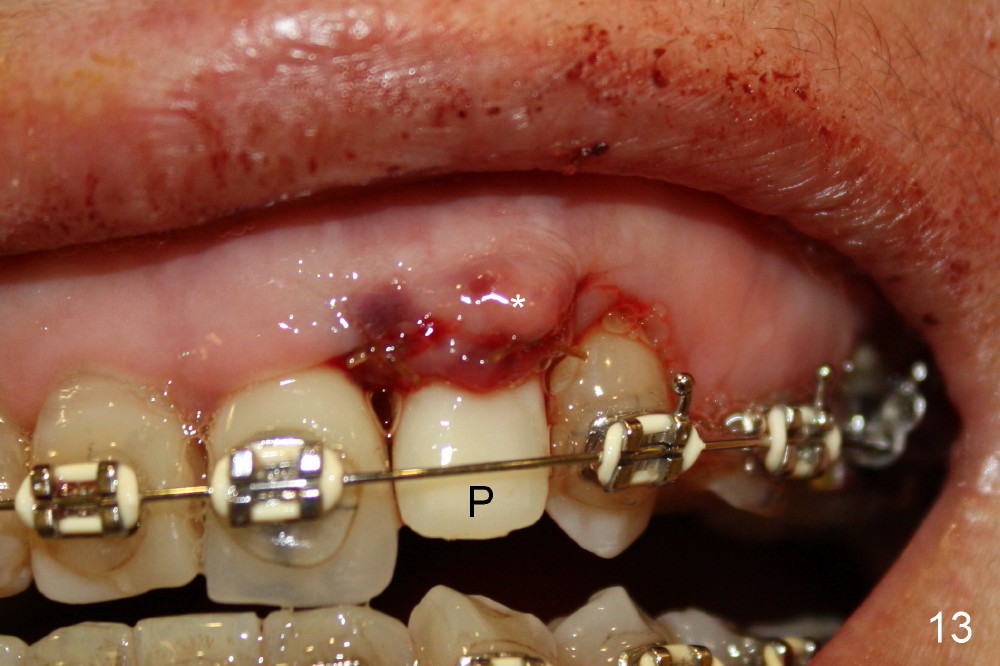

The buccal gap (Fig.11 *) is to be filled by allograft before insertion of an angled abutment (3.9 mm 25 º 3 mm cuff, Torx A type, Fig.12). The shoulder of the abutment is at the crest level (*). A longer cuff (4 or 5 mm) would be more appropriate. The gap buccal to the shoulder of the abutment is closed by further bone graft. An immediate provisional is fabricated (Fig.12 P), followed by suturing the buccal flap (*), which should give bulk of the gingival tissue.